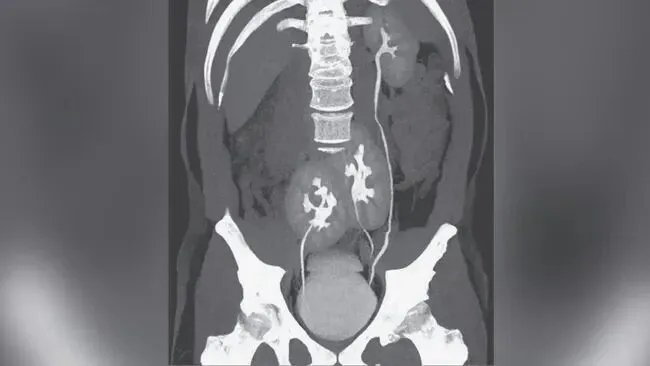

Qua siêu âm bụng và chụp CT, các bác sĩ phát hiện bệnh nhân có quả thận thứ ba, còn được gọi là "thận thừa". Quả thận thừa này nằm ở bên phải và được nối với quả thận phải ban đầu, tạo thành cấu trúc tổng thể hình móng ngựa.

Tuy nhiên, sự hiện diện của một quả thận phụ có thể làm tăng nguy cơ biến chứng đường tiết niệu trong một số trường hợp nhất định. Trong trường hợp này, các nghiên cứu hình ảnh cho thấy cả hai thận đều bị sưng, kèm theo hình thành sỏi. Sỏi thận là những cấu trúc tinh thể được hình thành khi nồng độ khoáng chất trong nước tiểu tăng cao. Sỏi nhỏ thường được đào thải qua nước tiểu, nhưng nếu chúng vẫn còn trong thận hoặc niệu quản, chúng có thể gây tắc nghẽn và thúc đẩy nhiễm trùng.

Trong trường hợp này, nhiễm trùng thận trái của bệnh nhân nghiêm trọng hơn, và có sự tích tụ sỏi trong niệu quản nối thận trái với bàng quang, cho thấy sự tắc nghẽn đường tiết niệu. Tắc nghẽn đường tiết niệu .Điều này có thể dẫn đến ứ đọng nước tiểu, tạo môi trường thuận lợi cho sự phát triển của vi khuẩn. Tình trạng "tắc nghẽn và nhiễm trùng chồng chéo" này được coi là yếu tố chính làm tình trạng bệnh nhân xấu đi. Cần lưu ý rằng thận phụ thường không trực tiếp gây ra nhiễm trùng đường tiết niệu, nhưng các bất thường về mặt giải phẫu đi kèm, chẳng hạn như khả năng thoát nước tiểu kém, có thể làm tăng nguy cơ sỏi và tắc nghẽn đường tiết niệu, từ đó tạo điều kiện cho vi khuẩn phát triển. Trong trường hợp này, sỏi và tắc nghẽn nhiều khả năng là nguyên nhân trực tiếp làm tình trạng nhiễm trùng xấu đi, trong khi thận phụ chỉ là một yếu tố tiềm ẩn.

Tính độc đáo của trường hợp này nằm chủ yếu ở hai khía cạnh. Thứ nhất, bản thân "quả thận thừa" cực kỳ hiếm gặp, với chưa đến 100 trường hợp mới được báo cáo trên toàn cầu mỗi năm; thứ hai, quả thận thừa đã hợp nhất với quả thận hiện có để tạo thành cấu trúc hình móng ngựa.Những trường hợp như vậy thậm chí còn hiếm gặp hơn , chỉ có rất ít báo cáo trong các tài liệu khoa học hiện có.